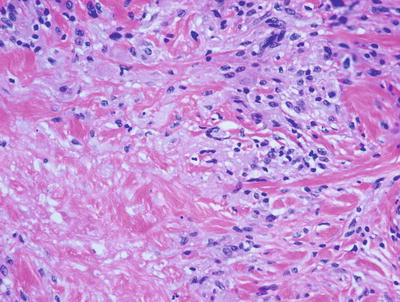

6.7.2 Histology

Palisaded neutrophilic and granulomatous dermatitis is often associated with collagen vascular diseases [71]. The histologic features include leukocytoclastic vasculitis associated with foci of collagenous degeneration in early lesions (Figs. 6.24 and 6.25). As lesions become more fully developed, areas of leukocytoclasis with fibrin deposition and degenerated collagen are found in the centers of palisading histiocytes (Fig. 6.26). Later lesions have fibrosis, minimal neutrophilic debris, and less cellularity.

Fig. 6.24

A diffuse infiltrate of histiocytes and neutrophils is seen throughout the dermis in palisaded neutrophilic and granulomatous dermatitis

Fig. 6.25

There is abundant interstitial mucin admixed with neutrophils and karyorrhectic debris in palisaded neutrophilic and granulomatous dermatitis